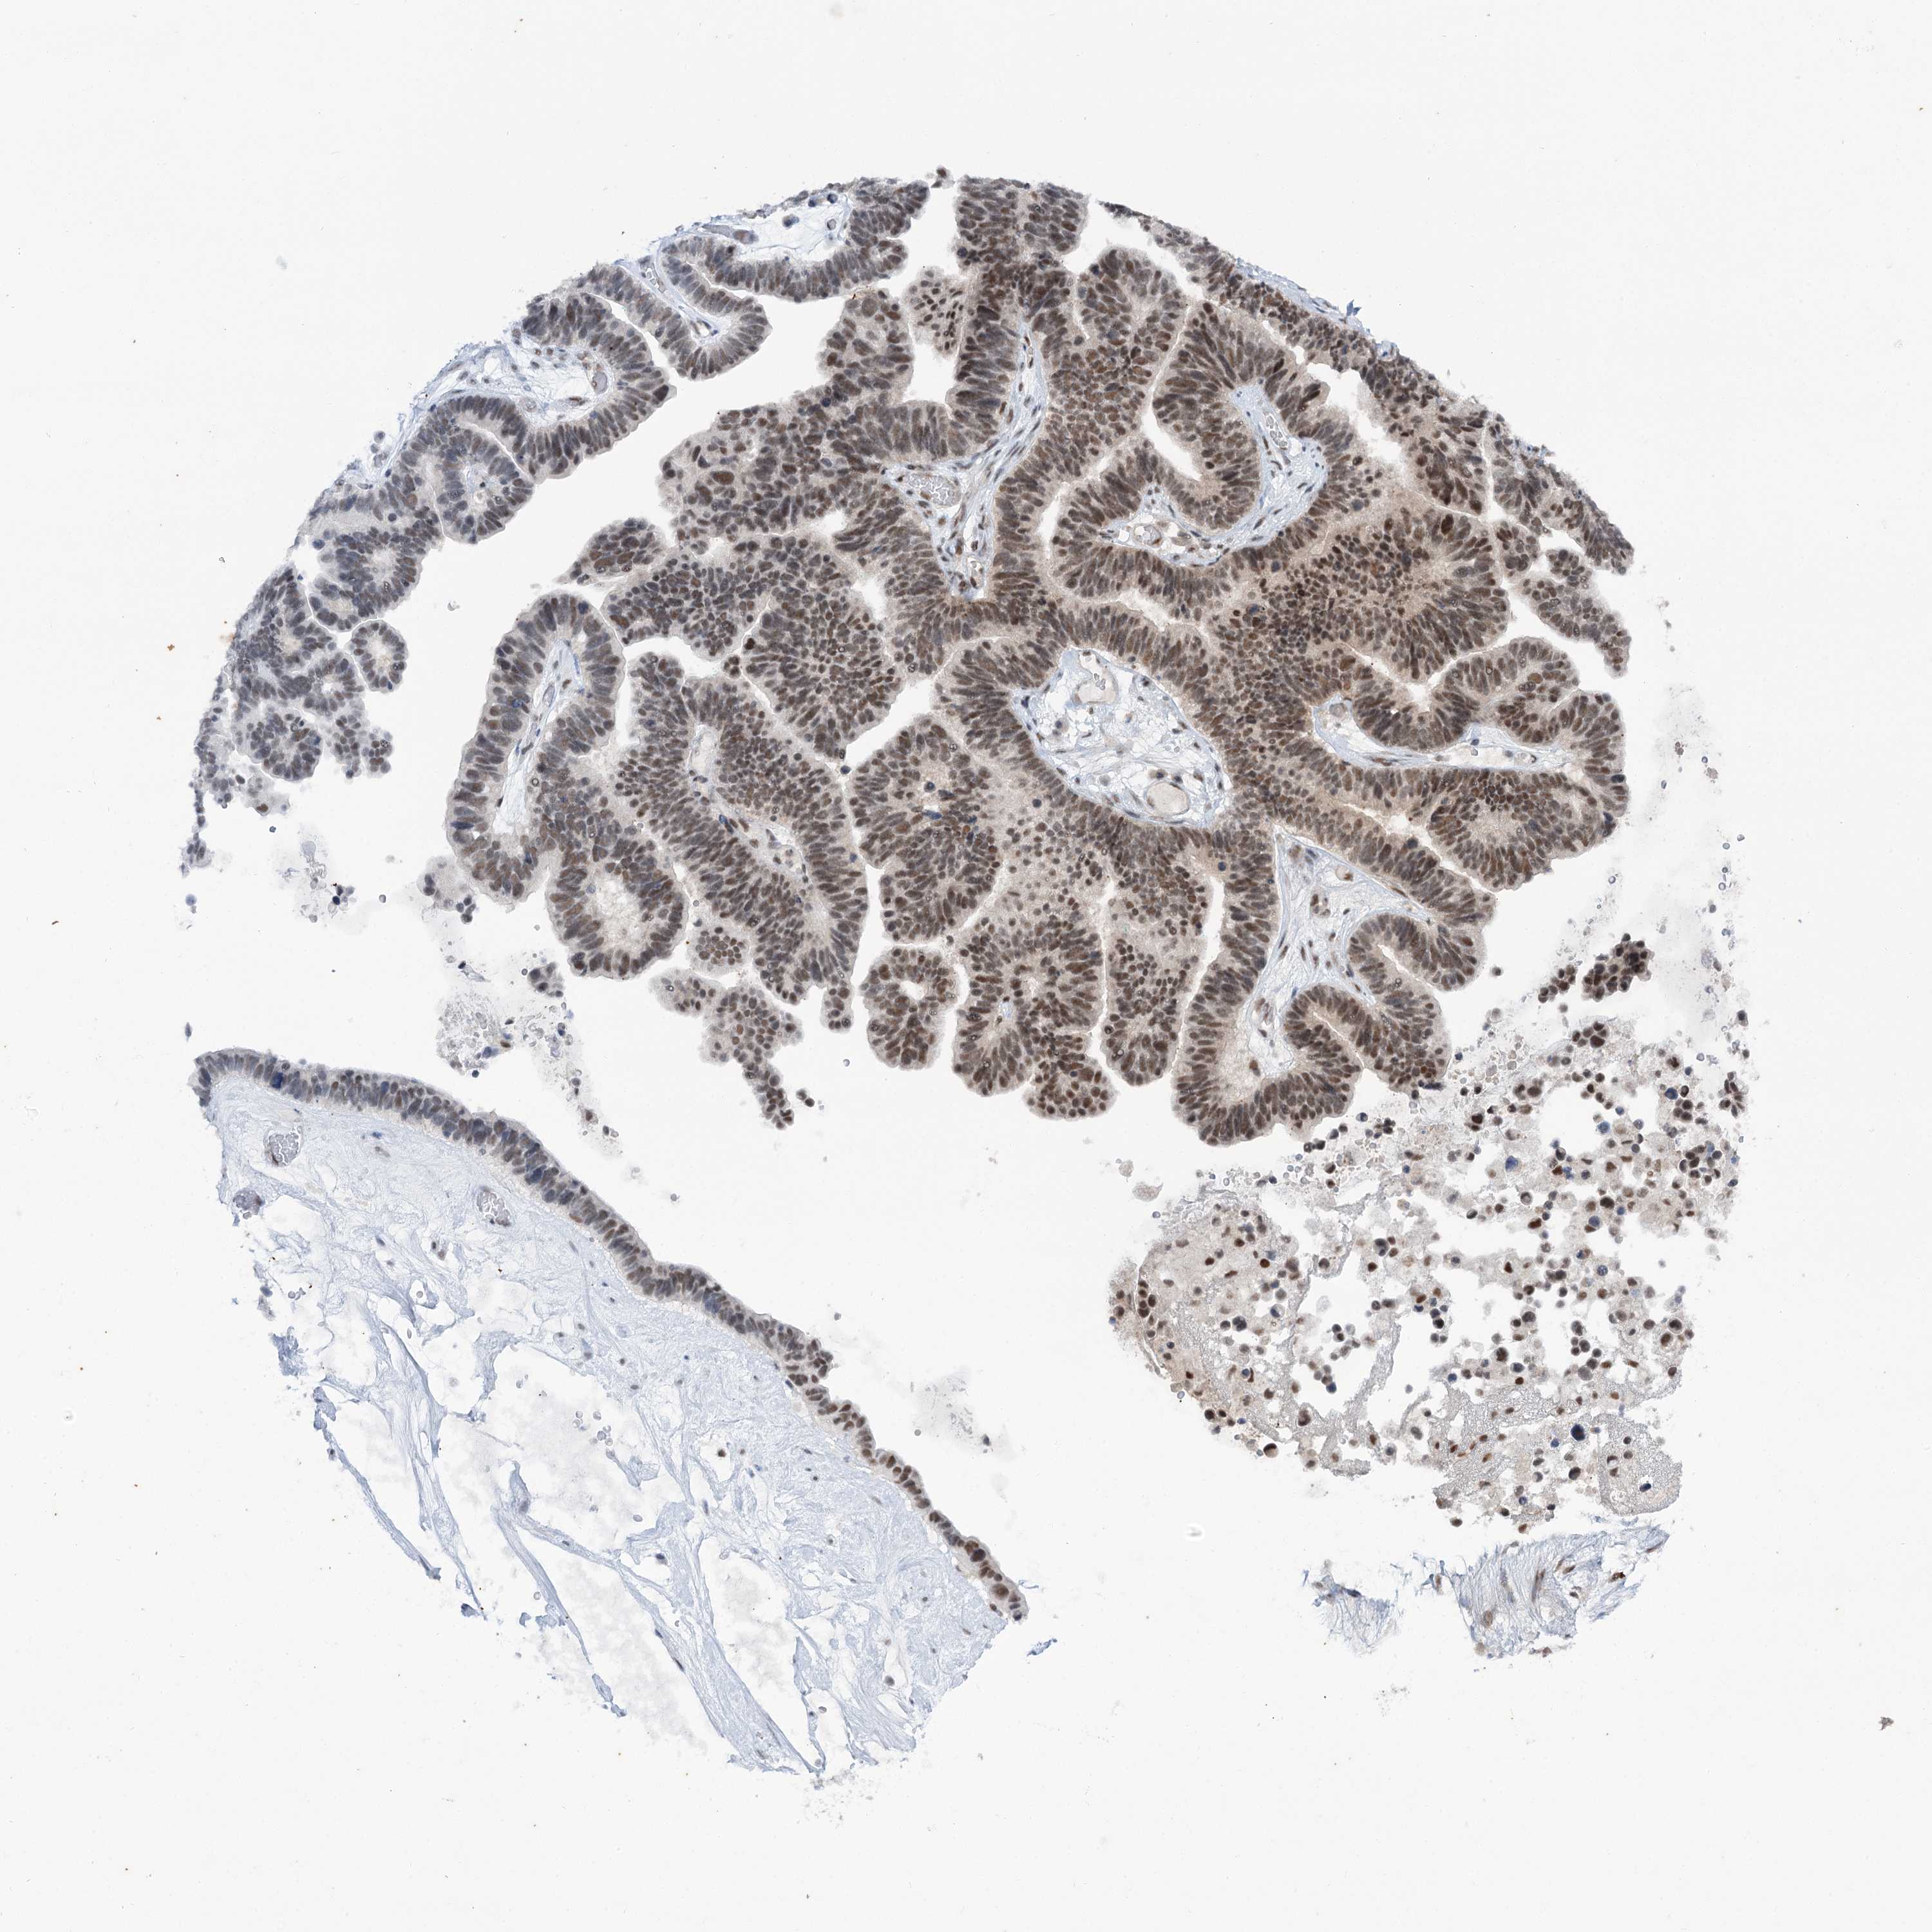

OVARIAN CANCER - Protein expressioni

A mouse-over function shows sample information and annotation data. Click on an image to view it in a full screen mode. Samples can be filtered based on level of antibody staining by selecting one or several of the following categories: high, medium, low and not detected. The assay and annotation is described here.

Note that samples used for immunohistochemistry by the Human Protein Atlas do not correspond to samples in the TCGA dataset.

Antibody stainingi

Antibody staining in the annotated cell types in the current human tissue is reported as not detected, low, medium, or high, based on conventional immunohistochemistry profiling in selected tissues. This score is based on the combination of the staining intensity and fraction of stained cells.

Each image is clickable and will lead to virtual microscopy that enables deeper exploration of all samples and also displays staining intensity scores, fraction scores and subcellular localization as well as patient and tissue information for each sample.

Antibody CAB037153

Cystadenocarcinoma, serous, NOS

Carcinoma, endometroid

Cystadenocarcinoma, mucinous, NOS

Carcinoma, NOS